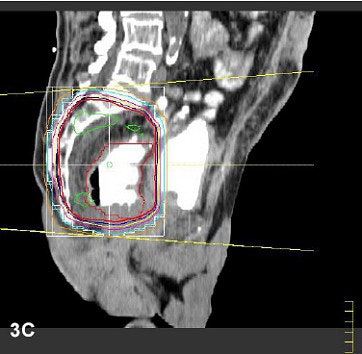

| The planning treatment volume included the primary tumor, presacral, and internal iliac lymphatics. Here, the thick red line represents 100% of the intended dose line, encompassing the targets. Images and captions courtesy of Dr. Andrew Kennedy. |